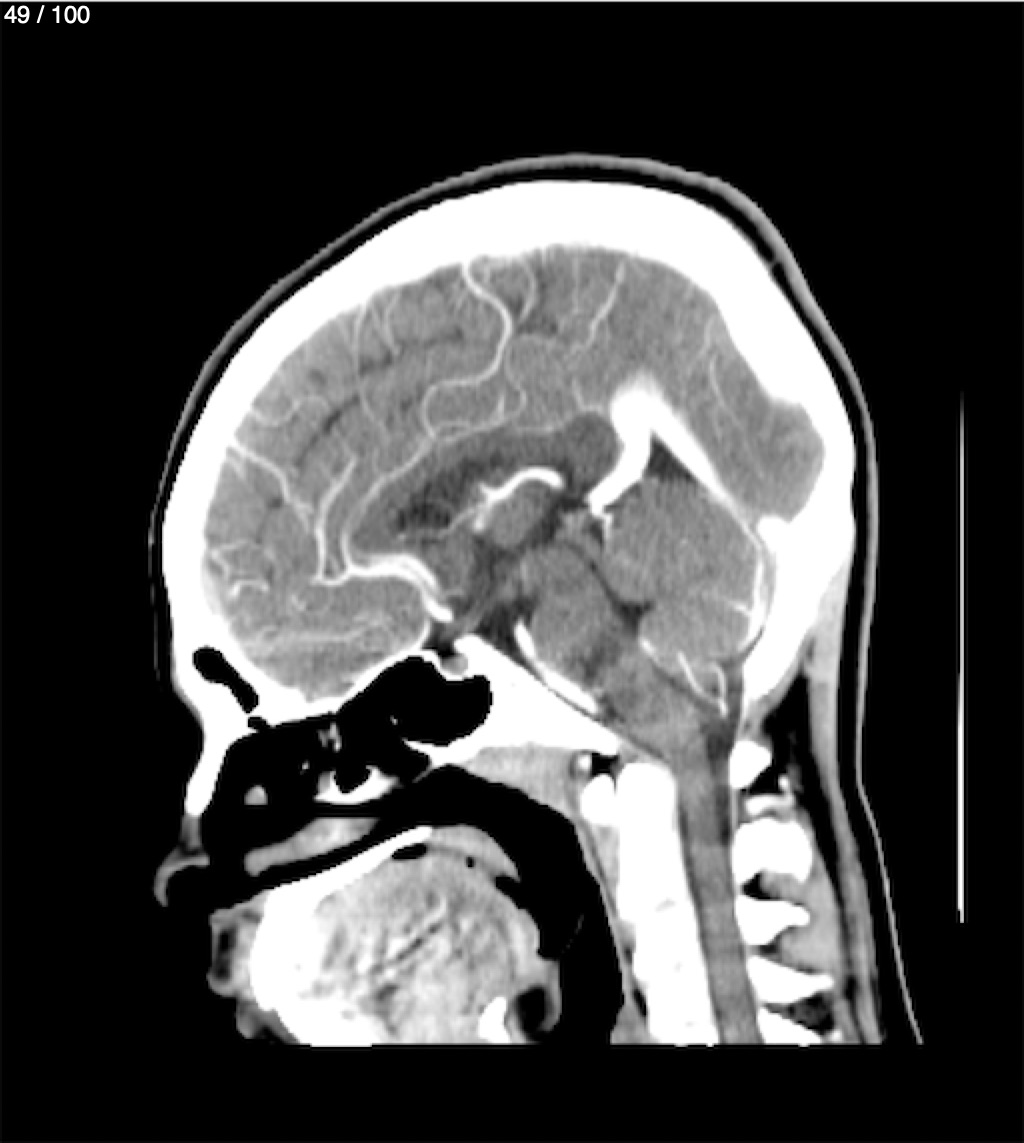

Fernando Daniel Gutierrez Caraba - Tc. Craneo Syc